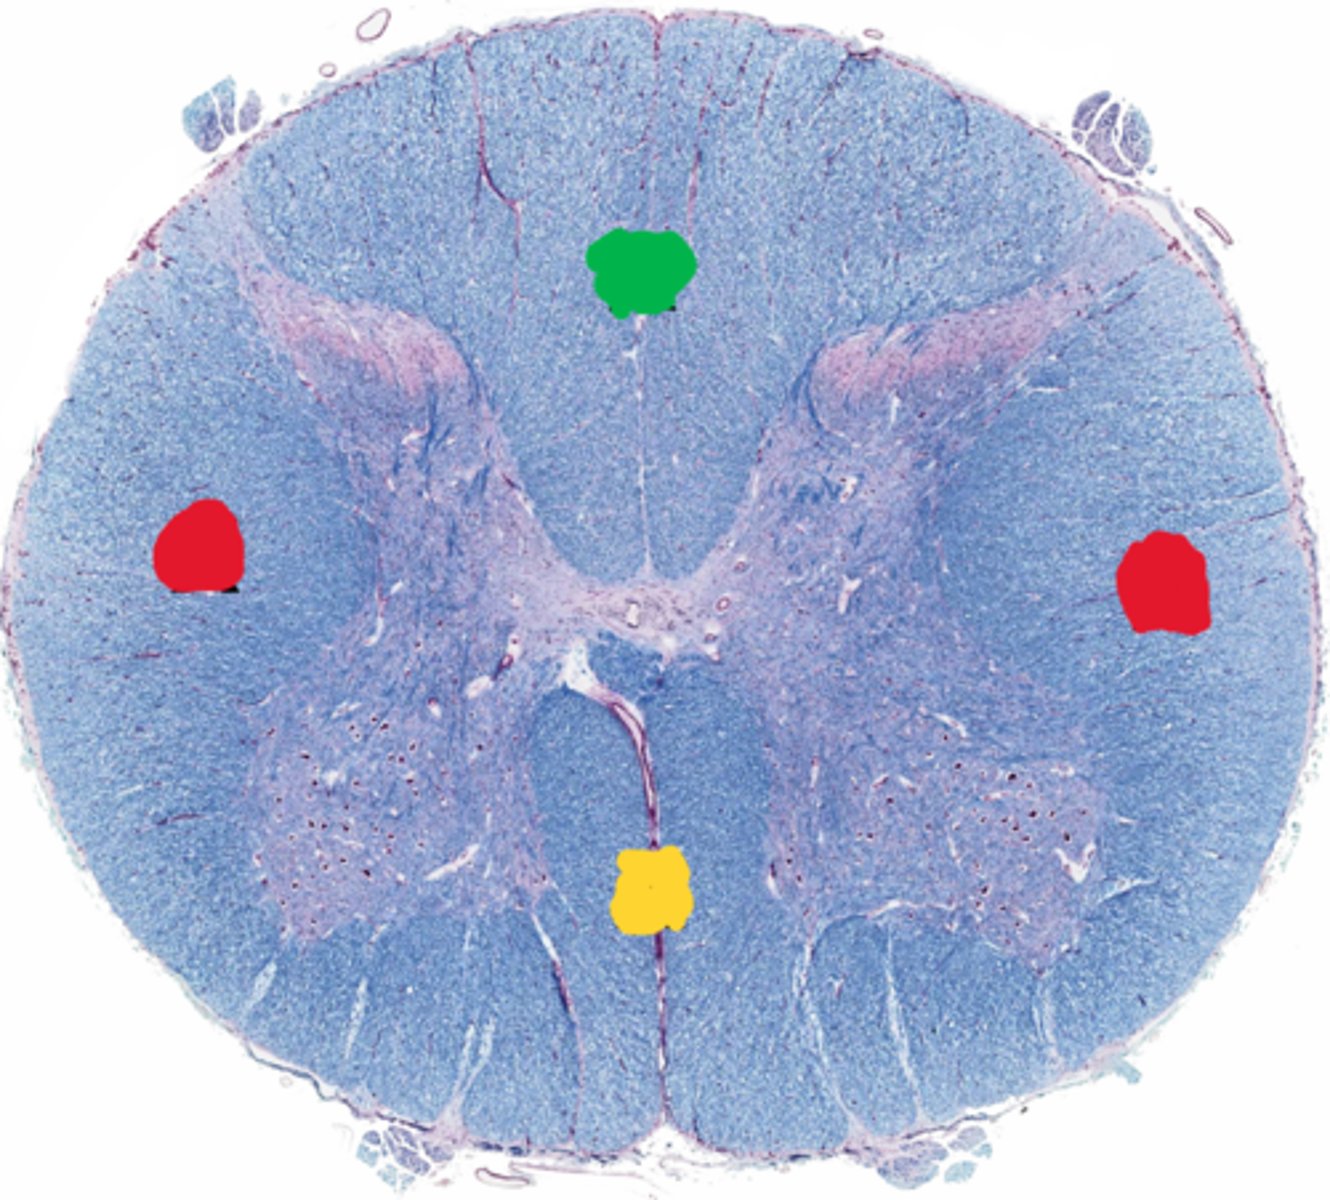

Posterior funiculus

Green

Anterior funiculus

Yellow

Lateral funiculus

Red

Posterior median sulcus

green

Anterior median fissure

red